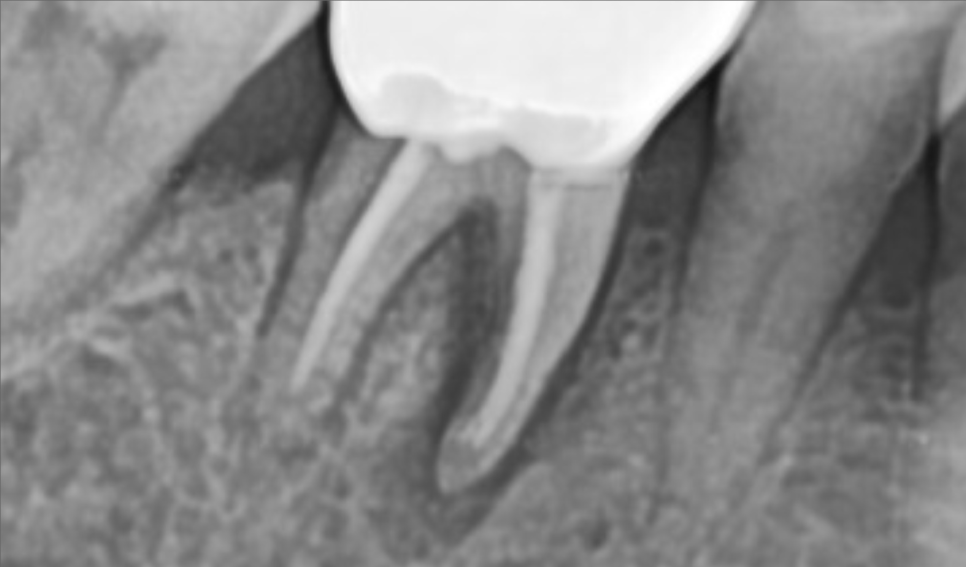

신경치료가 된채로 오래 사용한 뿌리는

쉽게 부서져서 발치가 어려운 케이스에 해당합니다.

살포시 발치를 완료하고 남은 뿌리가 없는지

X-ray를 찍어봅니다.

남은 뿌리없이 깔끔하게 나왔네요.